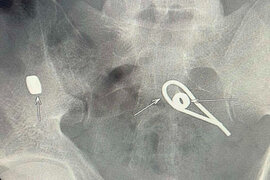

Bakıda kişi özünü öldürmək üçün dəmir parçaları uddu

Azərbaycanda dəhşətli intihara cəhd hadisəsi olub. xəbər verir ki, bir kişi intihar etmək məqsədilə iki metal qayka və bir ədəd əyilmiş məftil udub. O dərhal xəstəxanaya yerləşdirilib. Rentgen müayinəsi zamanı kişinin bağırsaqlarında udduğu metal parçalarının yeri müəyyənləşib. Hazırda həkimlər meta